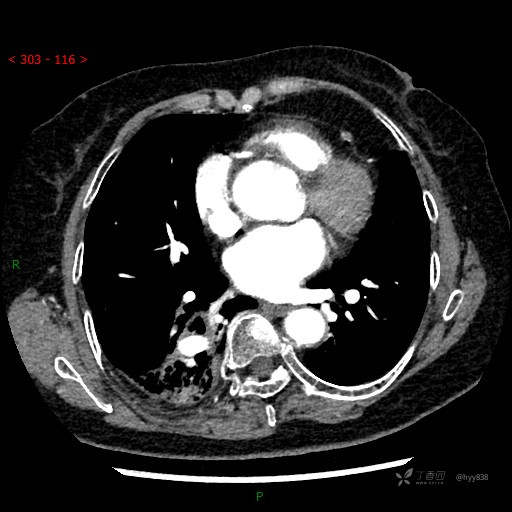

增强动脉期